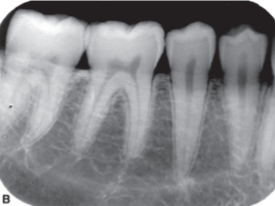

Which root appears disproportionately longer?

Palatal roots, compared to buccal roots

___ projection geometry produces images that are more reliably accurate for periodontal bone level evaluation than ____

BTW; PAs